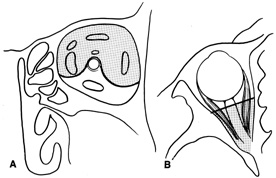

Fig. 7. Coronal schematic view demonstrating major vessels penetrating periorbita and traversing the extraperiosteal space that may be encountered during periorbital elevation. (A, zygomaticotemporal artery; B, zygomaticofacial artery; C, communicating branch of infraorbital artery: D, supraorbital artery: E, posterior ethmoidal artery: F, anterior ethmoidal artery.)